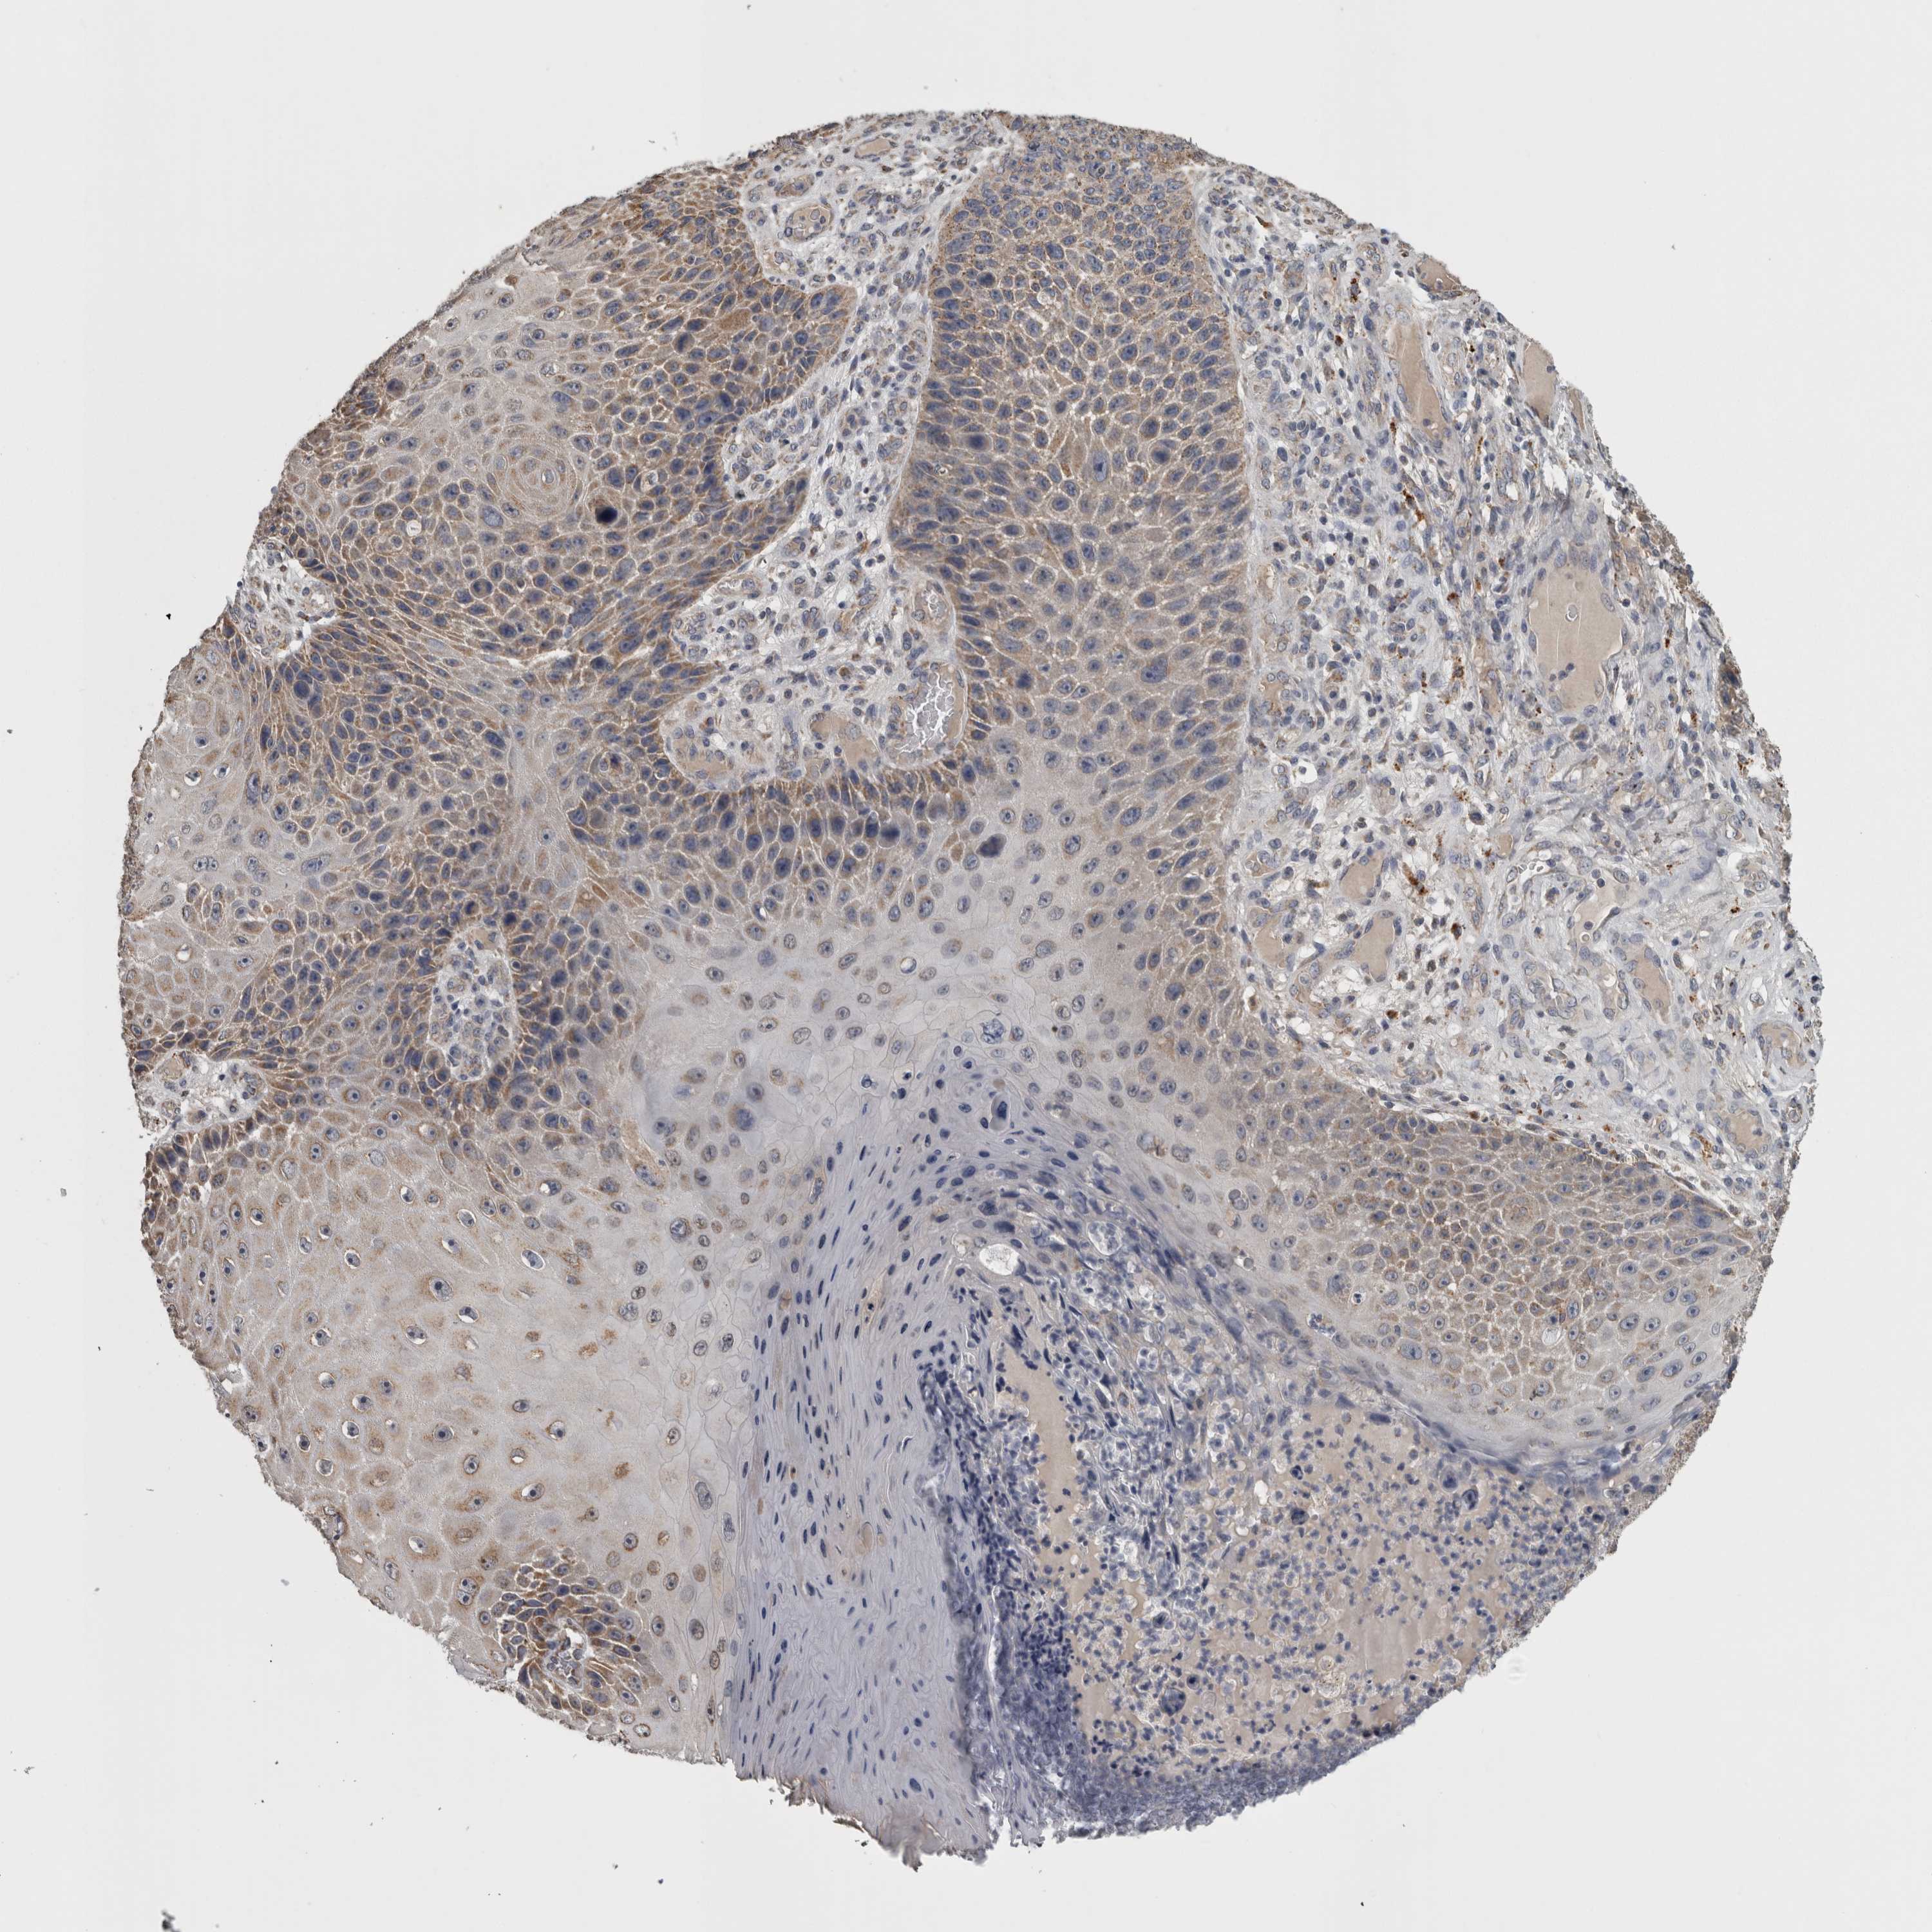

SKIN CANCER - Protein expressioni

A mouse-over function shows sample information and annotation data. Click on an image to view it in a full screen mode. Samples can be filtered based on level of antibody staining by selecting one or several of the following categories: high, medium, low and not detected. The assay and annotation is described here.

Antibody stainingi

Antibody staining in the annotated cell types in the current human tissue is reported as not detected, low, medium, or high, based on conventional immunohistochemistry profiling in selected tissues. This score is based on the combination of the staining intensity and fraction of stained cells.

Each image is clickable and will lead to virtual microscopy that enables deeper exploration of all samples and also displays staining intensity scores, fraction scores and subcellular localization as well as patient and tissue information for each sample.

Antibody CAB025217

Squamous cell carcinoma, NOS